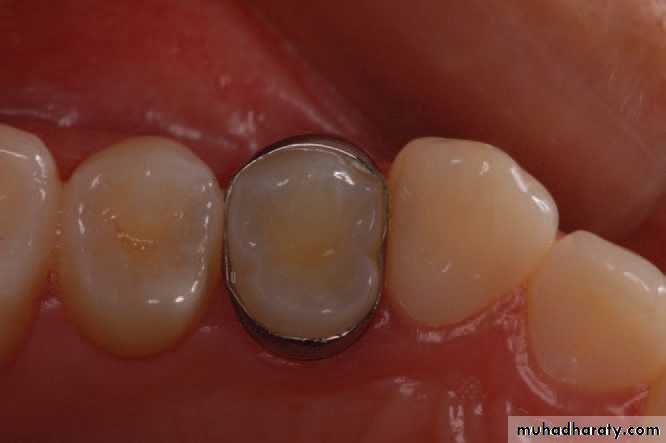

Initial view of the nonrestored tooth 24.Periapical radiograph of left maxillary premolars. No significant findings were present .

Bite test using a wooden wedge revealed pain in tooth 24.A crack was observed under transillumination . On the occlusal surface of tooth 24, from a mesial to distal orientation.

A stainless steel orthodontic band was cemented to confirm the diagnosis. The patient could bite without pain after this procedure.A cone beam computed tomography showing the crack in

a mesial-distal direction, involving the mesial, occlusal, and distal faces.Cracked tooth

Using a rubber dam, the crack was better visualized bygiving a contrasting color to background and keeping the tooth

dehydrated.

a): Transillumination was useful to confirm the defect removal during the cavity preparation, until no more cracks were visualized.

b): Completed MOD cavity preparation

Treatment completed

The tooth received a provisional restoration, and thepatient tested the tooth for 21 days.

After the symptoms were eliminated, a direct bonded

MOD composite restoration was performed